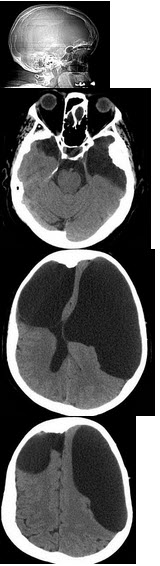

四岁男孩,因步态不稳,构音含糊就诊。该患儿孕35周时由于胎动减少而剖宫产,出生体重2100g,Apagar评分6分,5min后评分9分。患儿9个月会坐,3岁学步。体检:足尖行走,双下肢张力增高,有踝阵挛,双侧病理征阳性。 根据CT表现,最可能的诊断是( )

A:小脑扁桃体下疝

B:脑性瘫痪

C:颅底凹陷症

D:扁平颅底

E:先天性脑积水